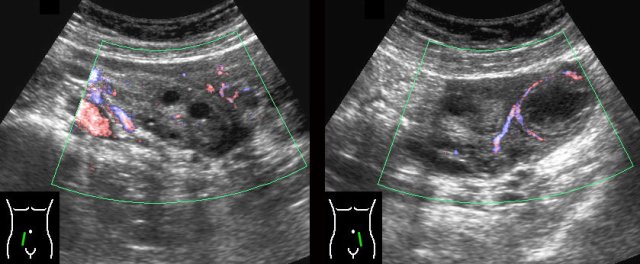

In women of the fertile age the normal inactive ovaries show moderate vascularization (left image).

During the pre-ovulatory phase the dominant follicle can be identified by its “ring-of-fire” (right image).

Luteal body

After the ovulation the dominant follicle becomes smaller (left) and in the absence of pregnancy, turns into a crenulated luteal body (right).